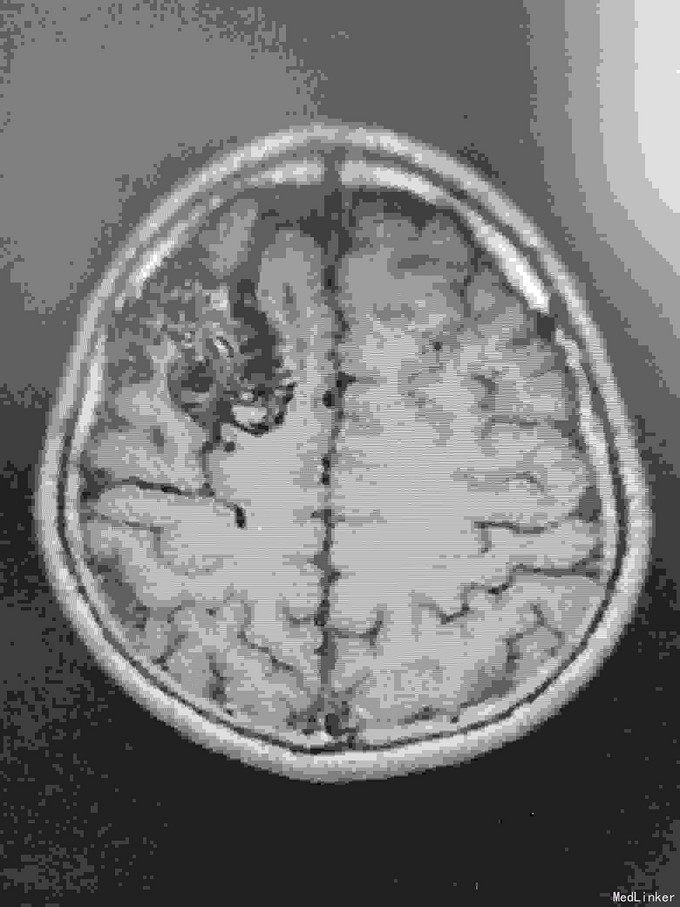

右额AVM

男,23岁。右额AVM。分次治疗。